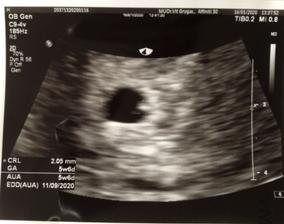

16.1.2020 první kontrola

3.3.2020 1.screening, čípek 40mm